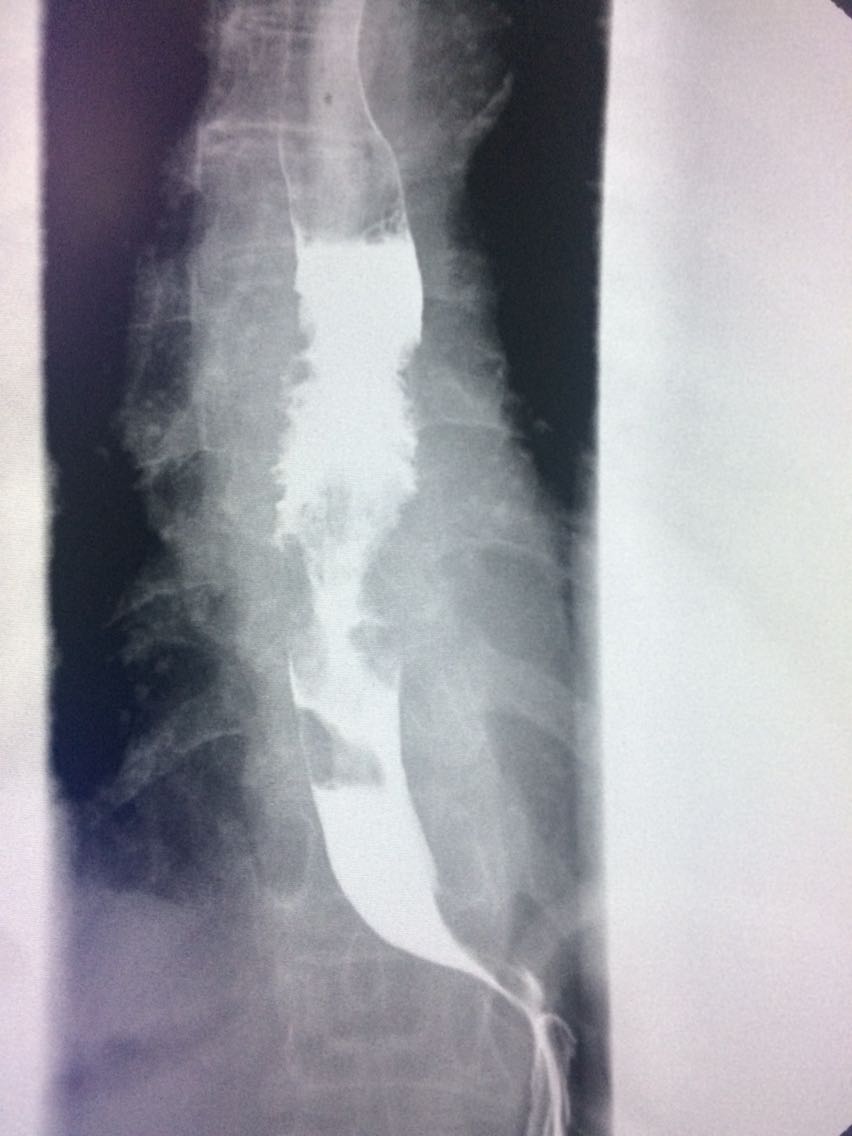

查体未见明显异常。 上消化道造影如图。

诊断食管癌。 造影剂逆流入胆道。